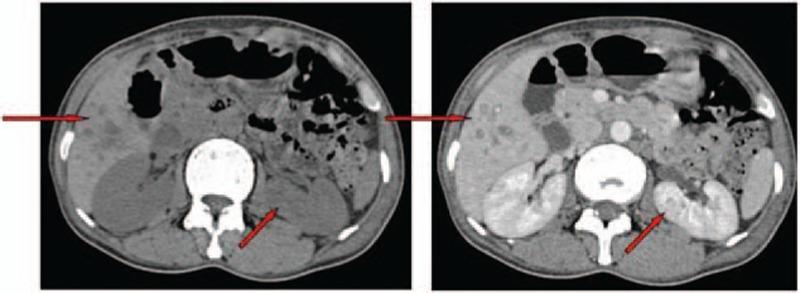

Hypereosinophilic syndrome (HES) can be fatal, particularly when eosinophils infiltrate vital organs and/or if extensive thrombosis develops. However there are no standard recommendations for the use of anticoagulant therapy of HES in the setting of thrombosis.

METHODS

We herein present a case of a 46-year-old female who presented with marked peripheral eosinophilia with symptoms of multi-organ infiltration and extensive deep venous thrombosis (DVT). In this case, evaluation was carried out before the diagnosis was established, and timely standard-dose corticosteroids combined with a new oral anticoagulant (NOAC) therapy were carried out.

These measures resulted in a rapid response and long-term disease control.